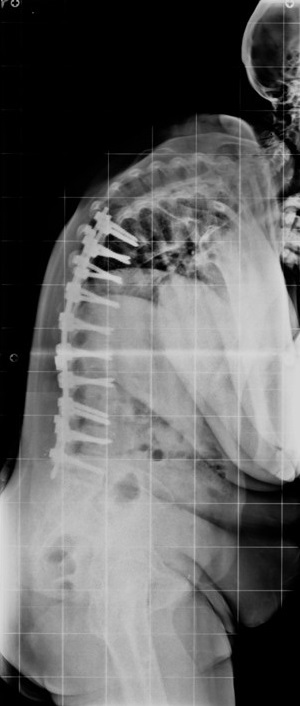

60 Yaşında Kadın Hasta

Ameliyat Sonrası